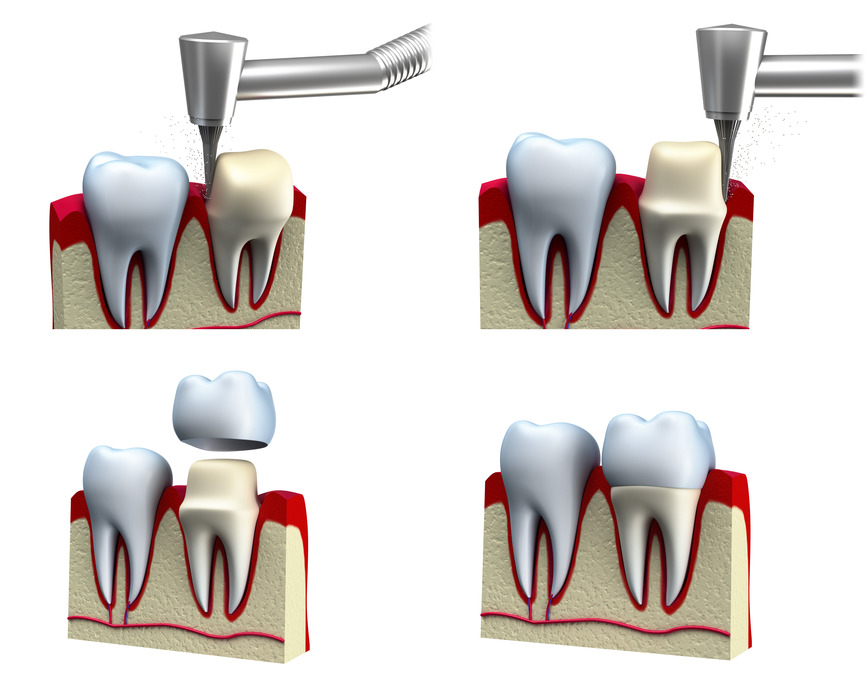

A crown, often referred to as cap, is a restoration that covers the tooth to provide more support and return the tooth to a normal size and shape. They are often indicated when a tooth has been severely decayed, damaged or has required root canal therapy. When a tooth missing, the surrounding teeth can be crowned with a center piece taking the place of the missing tooth or teeth. This is called a bridge.